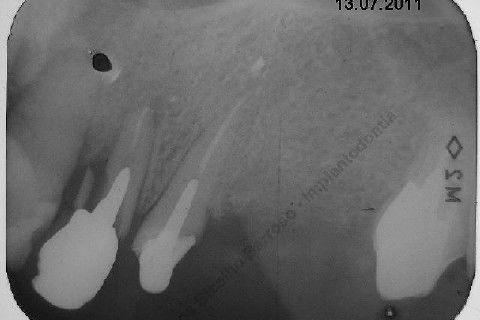

Paciente 66 anos, sexo feminino, procurou meus serviços para instalação de implante e coroa sobre implante na região do dente 22 com fratura radicular. Existem indicações para mais implantes mas a paciente está inrteressada no momento pela resolução deste caso.

Inicalmente estava planejado um implante cone morse 3.5 X 15,0 EX, mas resolvi experimentar um implante HI oferecido pelo vendedor da Bionnovation, como brinde (ele soube que estou preferindo o cone morse mas não trabalham com este sistema), e não consegui carga imediata neste implante. O travamento não foi satisfatório, ficou com um pouco mais de 20 N, menos de 25 N. Apesar desta ocorrência isto não significa que dará problema, apenas não fiz com carga imediata, aguardaremos 4 meses para a osseointegração.

Se o implante utilizado fosse o CM EX 3.5 X 15,0, além deste tipo de implante possuir característica autorosqueante, promovendo pelo seu design um melhor travamento, o seu comprimento de 15mm + 2mm infraósseo, conseguiríamos 6 mm de travamento em osso "virgem" (comprimento da raiz era de 11 mm) e travaria na cortical nasal. Mas este que usei, hexágono interno cônico, fica ao nível do rebordo; o maior que fabricam (comprimento de 15 mm), não apoiou em osso cortical e não é autorosqueante como o EX da Neodent.